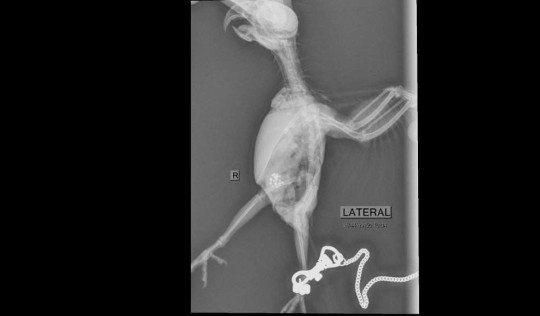

Bác sĩ thú y Kuntita Paveenasakorn đã tiếp nhận và chụp X-quang cho Frosty. Nhìn vào phim chụp X-quang, bác sĩ thấy rất nhiều dị vật giống như hạt trong bụng của nó nên anh liền đưa con vẹt đi mổ khẩn cấp.

Ca phẫu thuật kéo dài 2 giờ và thứ được gắp ra khiến bác sĩ lẫn chủ của Frosty sốc nặng. Bởi lẽ, bác sĩ gắp ra được 21 viên kim cương, mỗi viên khoảng 0.2 carat, từ bụng của chú vẹt. Hóa ra, con vẹt đã đột kích hộp trang sức của chủ nhân và lấy đi những viên kim cương trên chuỗi vòng cổ.

Ảnh chụp X-quang của con vẹt.